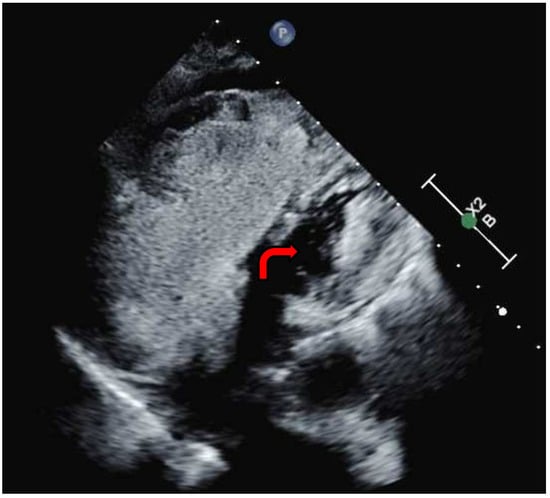

In light of these findings and with a suspicion of a mixed presentation of Group I and Group II PH, the decision was made to promptly wean pulmonary vasodilators. The patient was maintained on inhaled nitric oxide and norepinephrine. However, repeated attempts to reduce vasopressor dosage and epoprostenol resulted in persistent hypotension and severe hypoxia. A multidisciplinary meeting was convened to establish the goals of care and evaluate the patient’s clinical trajectory and available therapeutic options. Review of the prior echocardiogram, performed with a bubble study, revealed an intracardiac shunt (Figure 5, Video S1), consistent with an atrial septal defect (ASD). It was postulated that the pulmonary edema and worsening hypoxia could have been secondary to the intracardiac shunt, in conjunction with left ventricular dysfunction resulting from prolonged right ventricular failure. Consequently, a decision was made to resume titration of the epoprostenol, supported by the use of vasopressin and dopamine to sustain the mean arterial pressure above the mPAP, thereby minimizing intracardiac shunting and improving right ventricular perfusion.

Figure 5. Transthoracic echocardiography with agitated saline study (bubble study). The red arrow illustrates agitated saline in the left ventricle.

The following supporting information can be downloaded at: https://www.mdpi.com/article/10.3390/reports8010016/s1. Video S1: Transthoracic echocardiography with agitated saline demonstrating the presence of bubbles in the left ventricle.